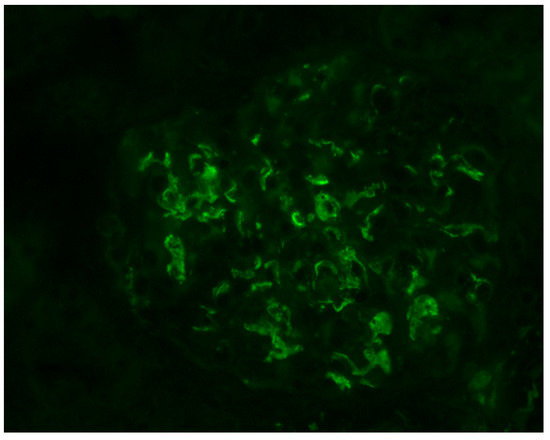

- Berger, J.; Hinglais, N. Intercapillary deposits of IgA-IgG. J. D’urologie Nephrol. 1968, 74, 694–695. [Google Scholar]